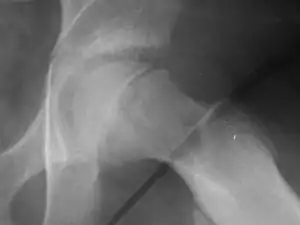

![]() | |

| X-ray showing a slipped capital femoral epiphysis, before and after surgical fixation. | |